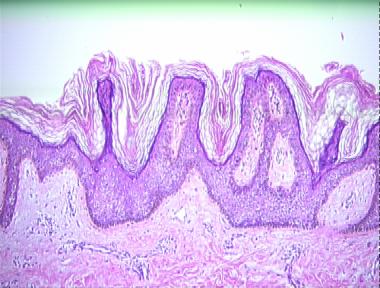

acanthosis nigricans

Histologic Features